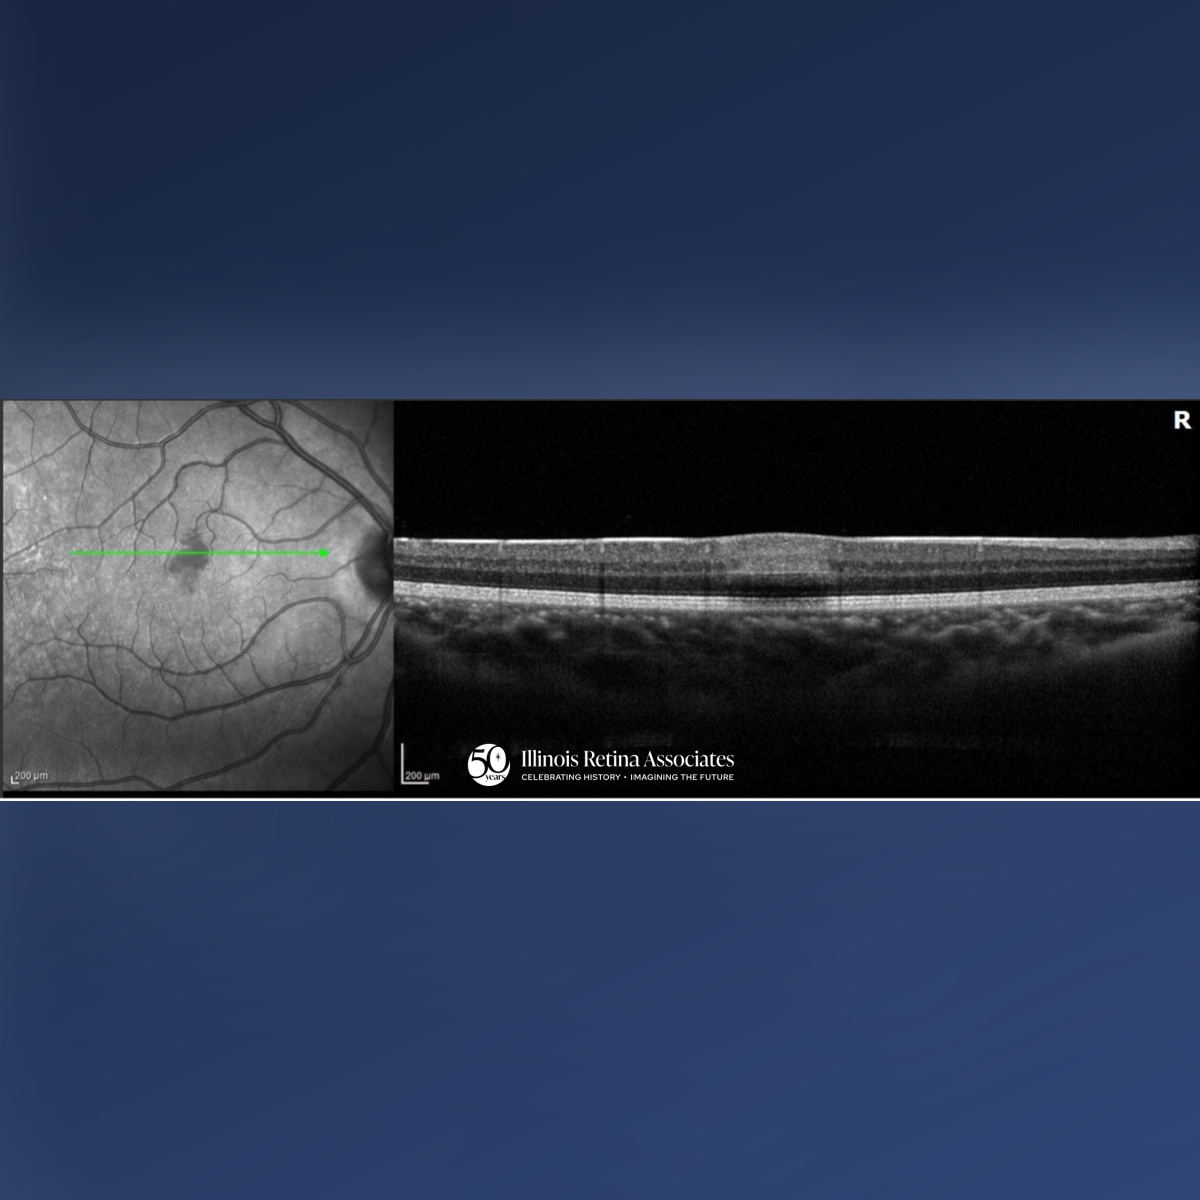

Visual acuity (VA) was 20/20 in both eyes (OU). Intraocular pressures and anterior segment exams were normal OU. Posterior segment exam OD demonstrated a cup to disc ratio (CDR) of 0.1 and a focal area of retinal whitening just superior to the fovea. Posterior segment in the left eye (OS) revealed a CDR of 0.1 and was otherwise unremarkable. Ocular Coherence Tomography (OCT) OD was significant for a band-like hyperreflectivity of the inner retinal layers (Fig 1) and FAF OD demonstrated mild hypo-autofluorescence overlying the area of retinal whitening (Fig 2). OCT OS was unremarkable (Fig 3). The patient was referred to the emergency department for a stroke evaluation which was negative. He returned approximately one week later where his VA remained stable at 20/20, and OCT showed slight improvement of the inner retinal hyperreflectivity (Fig 4). His central scotoma, however, remained unchanged.

PAMM is an ischemic macular disorder affecting the inner nuclear layer, often presenting with a sudden paracentral scotoma with minimal VA loss.1 PAMM can affect a wide-range of individuals from healthy patients to those with underlying systemic or retinal vascular disease, including arterial or venous occlusion, diabetes, or hypotension.2 Diagnosis is image-based: acute OCT imaging shows band-like hyperreflectivity of the inner nuclear layer, followed by focal thinning. FAF may be normal or show subtle hypo-autofluorescence. OCT-A can reveal capillary plexus flow deficits.3 While generally self-limited, paracentral scotomas may persist despite preserved visual acuity, reflecting permanent middle retinal ischemic injury.1